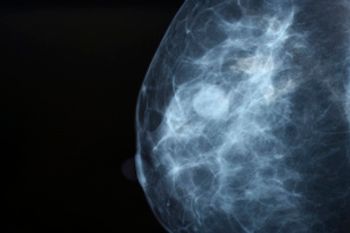

In a study presented at the annual meeting of the Radiological Society of North America (RSNA), researchers found that starting mammography screening at age 30 may benefit women with at least 1 of 3 risk factors: dense breasts, a personal history of breast cancer, or a family history of breast cancer.

Massachusetts General Hospital (MGH) is using artificial intelligence (AI) to process screening mammographies after a retrospective study found that AI can measure breast density—a risk factor for having tumors that could be missed during a scan—at the screening level of an experienced radiographer.

A new study offers insights into ways to improve breast cancer screening with a new understanding of how genetic risk variants affect disease progression and mode of detection. The study found that the presence of certain rare mutations was indicative of increased risk from interval breast cancers and death.